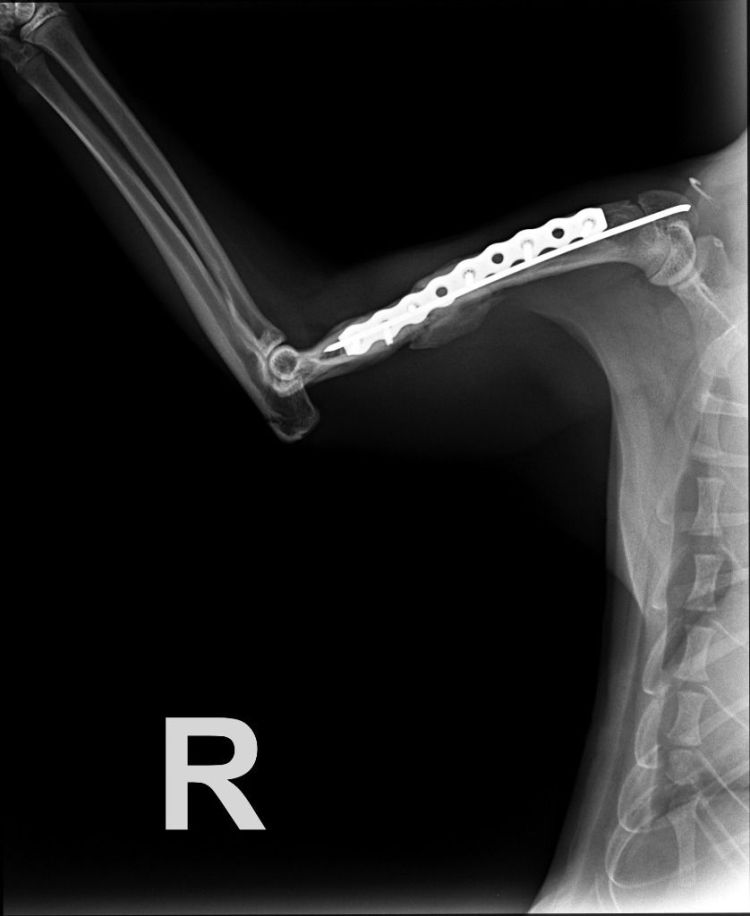

Beschreibung | Mauro wurde schwer verletzt in der Nähe einer betreuten Katzenkolonie gefunden. Er gehörte aber nicht zu dieser. So vermutet man, dass er dort ausgesetzt worden ist und er ziellos und desorientiert umherlief und so von einem Auto erfasst wurde. Natürlich hielt niemand and und man ließ ihn einfach an der Straße liegen. Mauro konnte sich bis an den Straßenrand schleppen. Glücklicherweise wurde er schnell von der Betreuerin der Katzenkolonie gefunden und zum Tierarzt gebracht. Er hatte einen Bruch des rechten Oberarmknochens. Mauro wurde auch gleich operiert und es wurde eine Platte eingesetzt (s. Röntgenbilder). Diese muss nicht entfernt werden. Zwischenzeitlich ist alles gut verheilt und er kann sein Bein wieder ganz normal benutzen und belasten. Er kann wieder rennen und springen. Mauro ist ein verspielter und geselliger Katermann. Er mag die Aufmerksamkeit des Menschen, liebt die Streichel – und Schmuseeinheiten und zeigt aber auch, wenn er nicht mehr möchte. Und das sollte man respektieren! Mauro ist ein guter Fresser und man kann ihn mit Futter bestens bestechen :-). Er versteht sich mit anderen Katzen bestens, ist sehr sozial, friedliebend, aber er ist auch eher selbständig. Zwar spielt er mit den anderen Katzen, aber er legt sich nicht zu ihnen ins Körbchen Wir suchen für Mauro eine Familie, wo er festes Familienmitglied sein darf. Da er seine Katzenkumpels gerne mag, aber nicht unbedingt mit ihnen kuscheln will, wären 1-2 andere, auch eher selbständige Kater in ähnlichem Alter genau richtig. Mauro wird auf keinen Fall als Einzelkatze vermittelt. Sollte noch keine Katze in ähnlichem Alter und Charakter in der Familie leben, vermitteln wir ihn auch gerne mit einem Kumpel aus seiner jetzigen Gruppe. Liebe Kinder sind sehr gerne gesehen. Hunde sind O.K., wenn sie ruhig sind und ihn in Ruhe lassen. Mauro soll Freigang in sicherer und ruhiger Umgebung bekommen. Es soll ein Haushalt sein, wo eine Katzenklappe vorhanden ist oder noch installiert wird. Er wird FIV und Leukose getestet, Tollwut, Schnupfen, Seuche und Leukose geimpft, entwurmt, gechipt und kastriert abgegeben. |